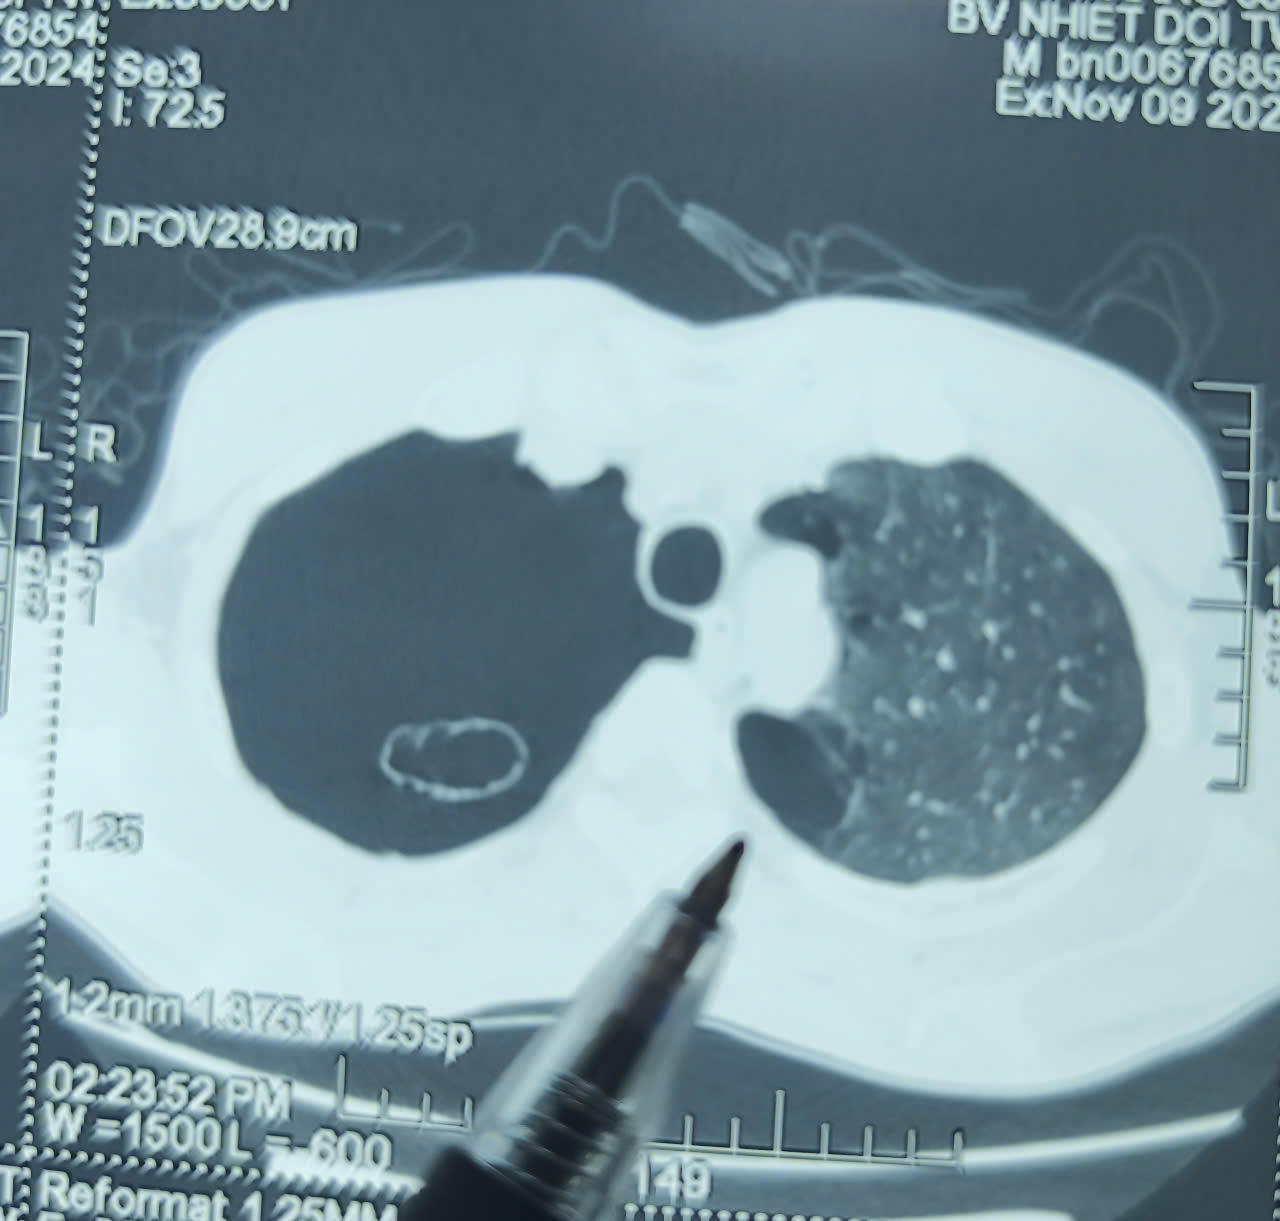

BSCKII Khiếu Mạnh Cường, bác sĩ chuyên ngành Ngoại - Lồng ngực, Khoa Ngoại Gan mật và Ung bướu, Bệnh viện Bệnh Nhiệt đới Trung ương cho biết: “Phổi của bệnh nhân có nhiều bóng giãn, phế nang có nhiều bóng khí. Trên bề mặt nhu mô phổi có nhiều điểm yếu cần phải tiến hành phẫu thuật nội soi lồng ngực nhằm tránh bị tái phát tràn khí màng phổi lại”.

Hình ảnh phổi của bệnh nhân. Ảnh: Thanh Thanh |